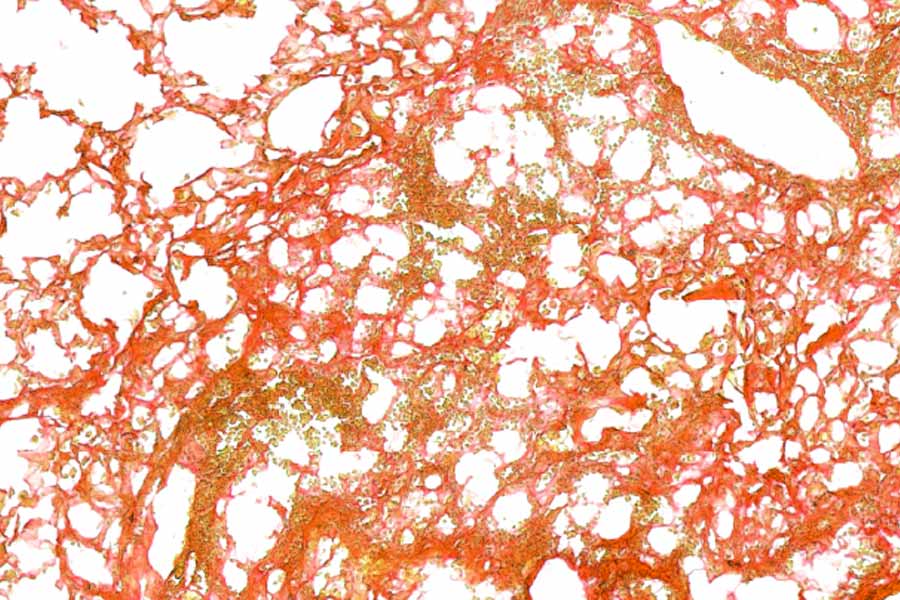

Area of mouse lung with established fibrosis.

In mice that already had lung scarring, PAIR2 not only slowed further damage but also partially reversed some of the fibrosis that had formed. The drug helped AT2 cells keep their identity, reduced the number of "in-between" cells, and significantly cut down the buildup of scar tissue.